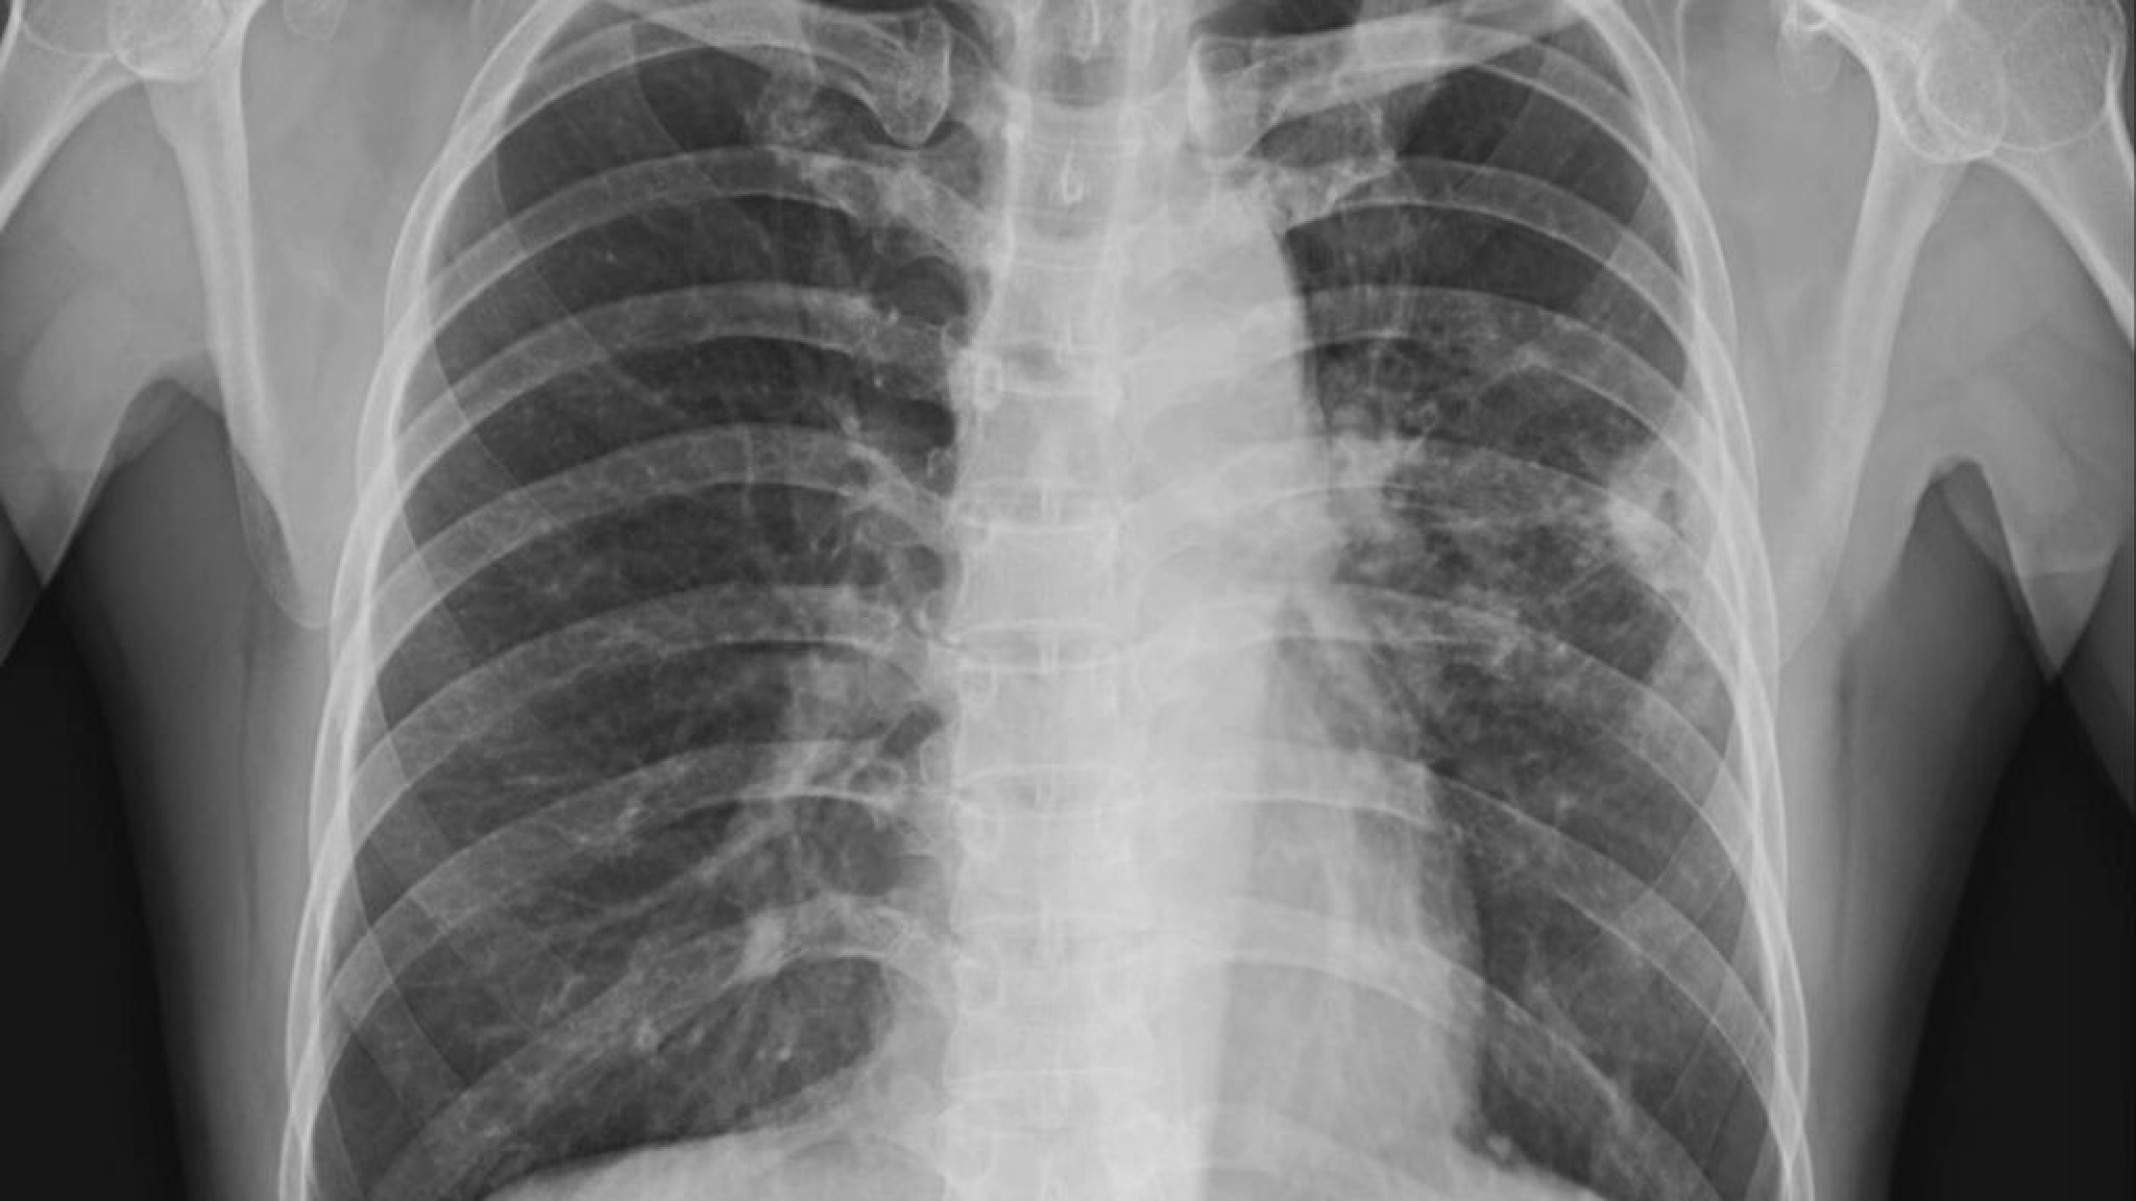

raio-x de cancer – depositphotos.com / Richmanphoto

O diagnóstico de uma neoplasia geralmente envolve uma combinação de exame clínico e métodos de imagem, como ultrassonografia, tomografia ou ressonância. No entanto, o passo mais importante costuma ser a biópsia. Nesse procedimento, o profissional de saúde retira um fragmento do tecido e o patologista analisa esse material ao microscópio. Esse estudo permite distinguir com precisão se se trata de uma neoplasia benigna ou maligna e qual é o tipo celular envolvido. Essa informação orienta a definição do tratamento mais adequado.